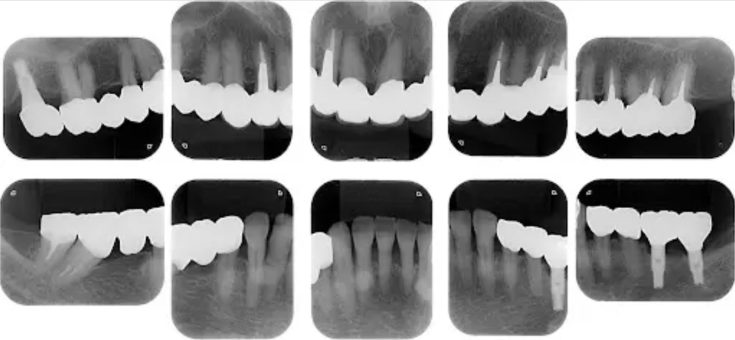

多数歯欠損のインプラント治療の症例(うえだ歯科)

| 治療内容 | 歯周病で骨の吸収が重度で保存不能なため抜歯、仮の入れ歯を作り、6ヶ月の抜歯窩の治療の後に、インプラントのCTによる診査診断を行い、下顎に6本インプラント埋入と同時に仮歯を入れる。その後、上顎は8本のインプラント埋入と同時に仮歯を入れる。左右上6はソケットリフトによる上顎洞拳上術を行う。その後免荷期間6ヶ月待ってセラミックを用いた上部構造作製、装着しメンテナンスに移行する。 |

| 想定されたリスク | 重度の歯周病により無歯顎になったため、プラークコントロール不良による、術後のインプラント周囲炎が懸念される。歯冠の部分はセラミックなため欠ける可能性がある。 |